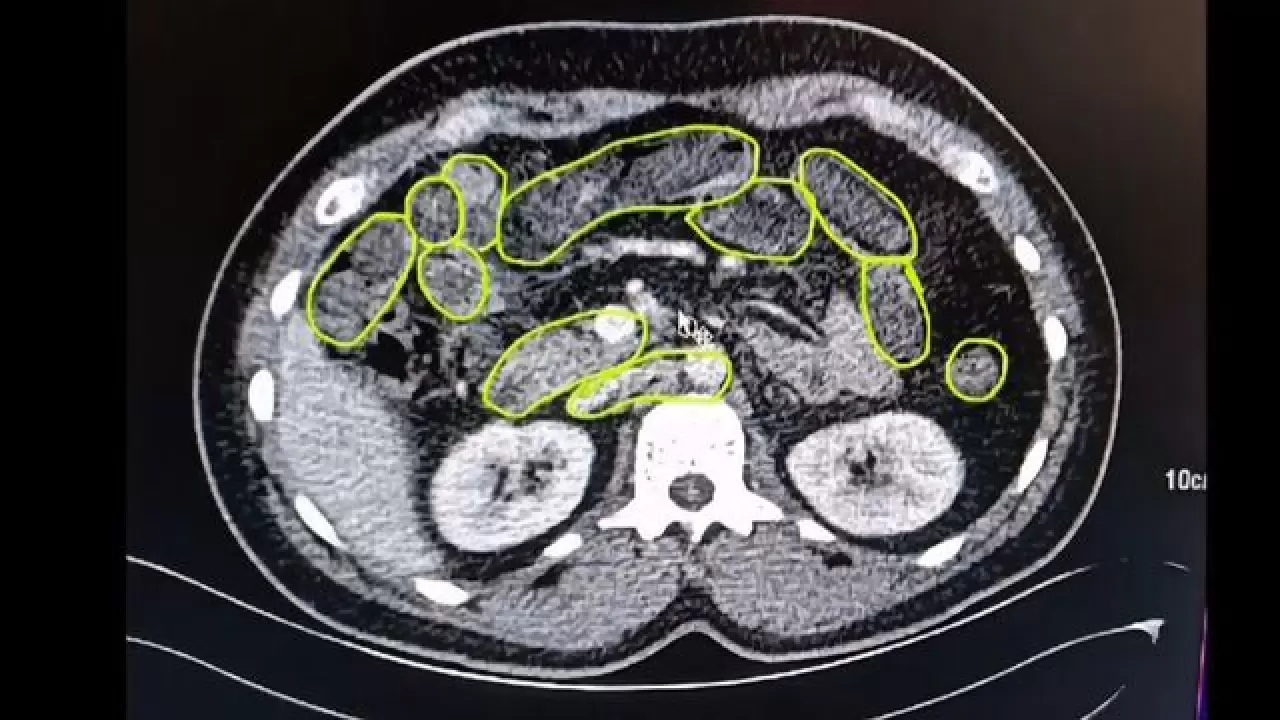

Şüphelilere hastanede gerçekleştirilen iç beden muayenesi sonucunda, mide ve bağırsaklarında kapsül formunda çok sayıda uyuşturucu maddeye rastlandı. Uzman ekipler, bu maddelerin vücut dışına çıkarılması için tıbbi süreci başlattı.